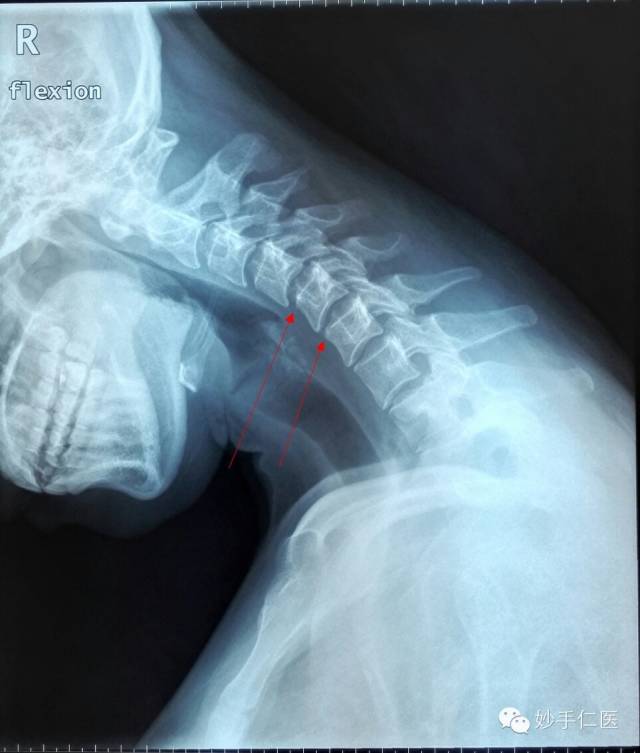

颈部低头位片子:颈5、颈6椎体前缘出现骨质代偿性改变(红色箭头)。清晰的显示了,长期低头姿势状态下,上位椎体对于下位椎体的挤压。骨质增生的出现,实际就是长期不良力学状态下的一种自身代偿。